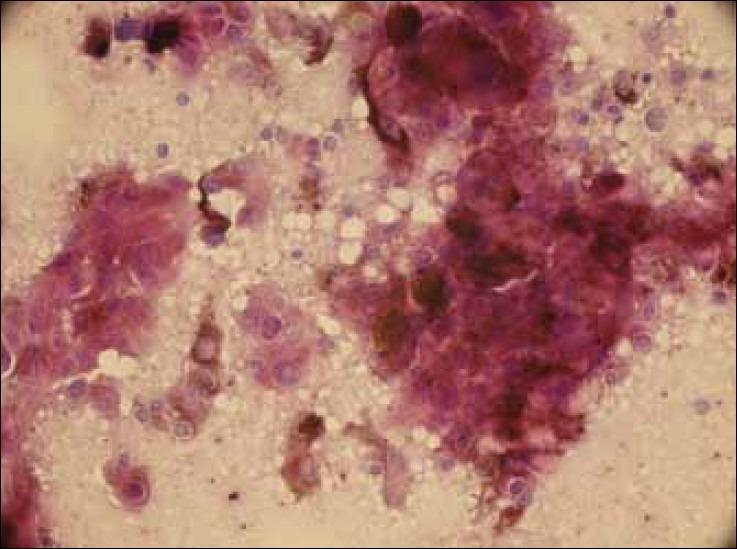

Metastatic malignant melanoma intraoperative imprint cytology of brain tumor.

J Cytol. 2012 Jul;29(3):192-3. doi: 10.4103/0970-9371.101170.

https://cdn.ncbi.nlm.nih.gov/pmc/blobs/1559/3480769/5f66296070f9/JCytol-29-192-g001.jpg